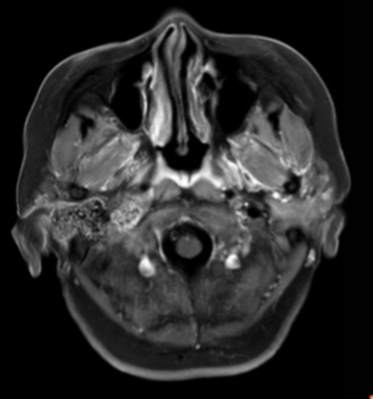

(2023-05-15 10:00,本院)行磁共振(颅脑)检查提示:右侧乳突区异常信号,考虑恶性、软骨来源肿瘤,软骨肉瘤可能性大。(集体讨论意见);脑内散在多发缺血灶。

(2023-05-12 10:15,本院)行CT(颅脑)检查提示:右侧颞骨广泛骨质破坏,伴巨大软组织肿块,性质待定,考虑肿瘤性病变,颈静脉球瘤?软骨源性肿瘤?请结合临床及病理进一步明确。

术后复查MRI: